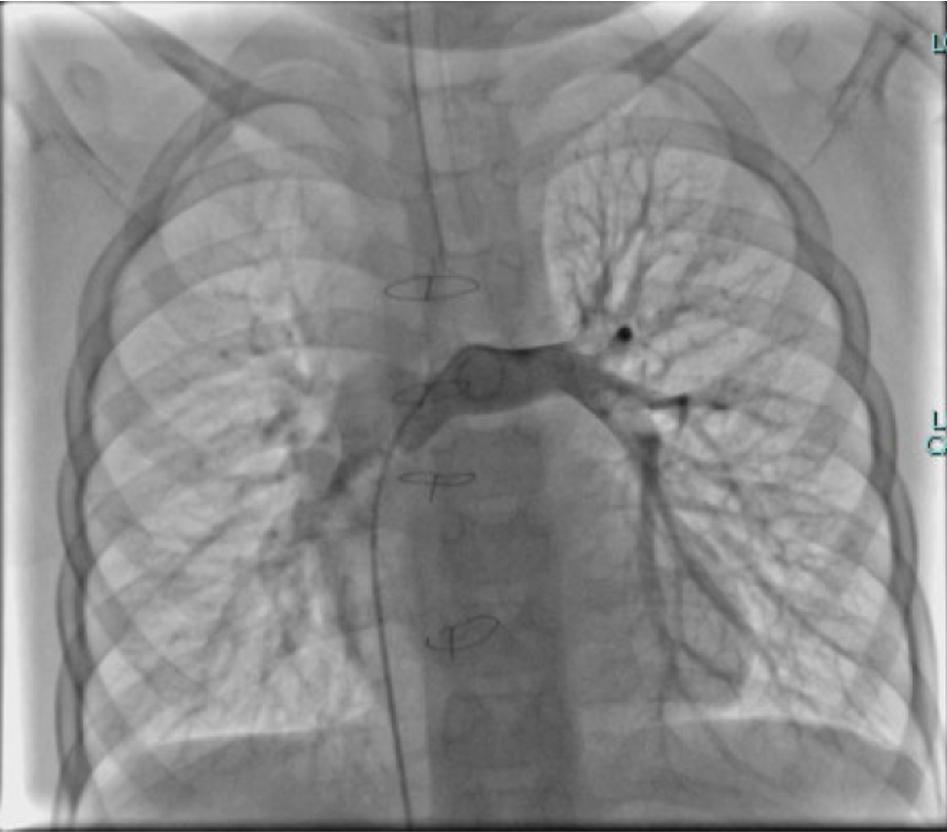

The operation was performed via a median sternotomy. Intraoperative exploration revealed that the ventricular septal defect was located in the inflow tract, distant from the aortic valve, making intracardiac tunnel construction infeasible; therefore, biventricular repair was not feasible. Under general anesthesia with hypothermic cardiopulmonary bypass, a total cavopulmonary connection (TCPC) was performed. The inferior vena cava was transected, and an 18-mm Gore-Tex conduit was anastomosed end-to-side to the right pulmonary artery, establishing a complete cavopulmonary circuit. Immediate postoperative oxygen saturation was approximately 75%. The total operative time was 6 hours and 14 minutes, with an aortic cross-clamp time of 50 minutes. The patient remained in the intensive care unit for 8 days and was discharged on postoperative day 19 after an uneventful recovery and stable hemodynamics. During a 2-year follow-up, peripheral oxygen saturation gradually increased and stabilized at 97–100%, with markedly improved exercise tolerance, resolution of digital clubbing, and normal skin color. Repeat cardiac catheterization confirmed unobstructed conduit flow and well-developed pulmonary vasculature. The previously extensive bilateral pulmonary arteriovenous malformations had completely resolved, pulmonary circulation time normalized, and pulmonary artery pressures measured 13/11/12 mmHg.